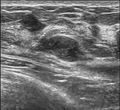

Since both fibroadenomas, and breast lumps as a sign of breast cancer can appear similar, it is recommended to perform ultrasound analyses and possibly tissue sampling with subsequent histopathologic analysis in order to make a proper diagnosis. Unlike typical lumps from breast cancer, fibroadenomas are easy to move, with clearly defined edges.[1][2]

Diagnosis

Cryoablation

The FDA approved cryoablation of a fibroadenoma as a safe, effective, and minimally-invasive alternative to open surgical removal in 2001.[25] During cryoablation, ultrasound imaging is used to guide a probe into the mass of breast tissue. Extremely cold temperatures are then used to destroy the abnormal cells, and over time the cells are reabsorbed into the body.[26] The procedure can be performed as an outpatient surgery using local anesthesia, and leaves substantially less scarring than open surgical procedures and no breast tissue deformation.

1. The lesion must be sonographically visible.